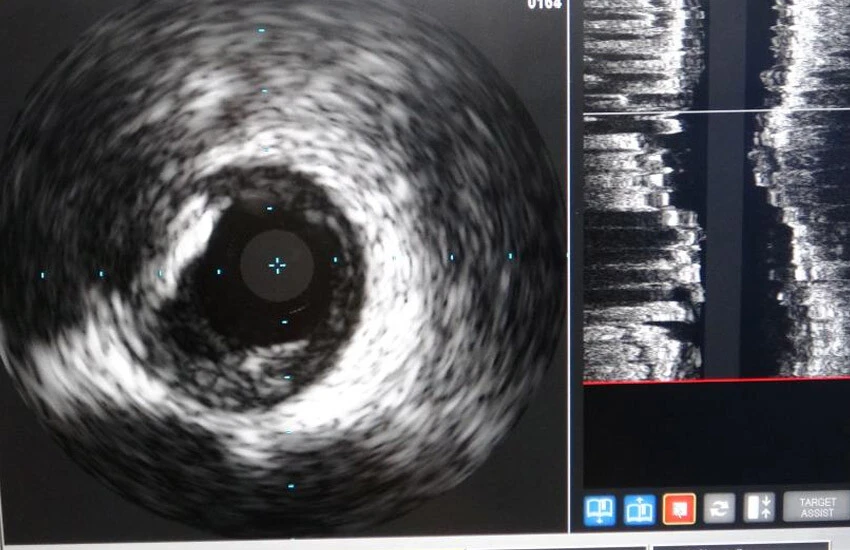

Son olarak Kalp Merkezi Ünitesine kazandırılan İVUS cihazı sayesinde kalp damarlarındaki tıkanma miktarı değerlendirilip, damar içindeki darlığın boyutu, damar içi yırtılmalar, stentlerin yerine tam olarak yerleşip yerleşmediği, damarların dallanma bölgesi ve damar başlangıç kısımları anjiyografiye göre daha iyi görülebilecek. Hastanede ilk kez kullanılan İVUS cihazı sayesinde hastaların dış merkeze gitmesine de gerek kalmadı.

İhlas Haber Ajansı’nda (İHA) yer alan habere göre, Hastane Başhekimi Doç. Dr. Remzi Sarıkaya, hastane bünyesindeki kalp merkezinin uzun zamandır hizmet verdiğini belirtti. Kalp merkezinde uzman hekimlerce çok sayıda başarılı işlemlere imza attıklarını ifade eden Başhekim Sarıkaya, “Kalp merkezimiz sadece Van iline değil, Doğu Anadolu Bölgesi’nin büyük bir kısmına hizmet veriyor. Bu merkezimiz 7 gün 24 saat çalışma prensibine göre çalışmaktadır. Tabii merkezimizde riskli ve komplike işlemler de yapılıyor. Bu komplike ve zor işlemlerde bypass olma şansı olmayan yüksek riskli hastalara işlem yapıldığında yeni teknoloji bize çok ciddi anlamda katkı sunuyor. IVUS cihazını, damar içini görüntüleyen bir ultrason sistemi olarak düşünebilirsiniz. Damarın içine gönderdiğimiz bir kateterle damarın içindeki darlıkları çok rahat bir şekilde irdeliyoruz. Bunun tabii ki ne kadar darlık oluşturduğunu, darlığa yol açan plağın morfolojisi hakkında bize ciddi bilgiler veriyor. IVUS bize ‘ana koroner’ dediğimiz ana damarın başındaki darlıklarda ciddi bir avantaj sağlıyor. Ana damarda darlık olduğu zaman mutlaka IVUS eşliğinde işlem yapmak lazım” dedi.

Kardiyoloji Uzmanı Dr. Gürkan İmre ise İntravasküler ultrasonun Türkiye'de ve dünyada sadece gelişmiş merkezlerde kullanılan bir yöntem olduğunu belirterek, “Kalbin içerisine bu ultrasonu gönderdiğimizde damar içerisindeki darlığın, plağın ciddiyetini görebiliyoruz.” şeklinde konuştu.